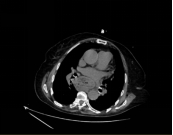

膈肌上有个让食管通过的“裂孔”。当裂孔变大,胃甚至其他腹腔器官会往胸腔里挤,就像“胃跑到胸腔里”一样——这就是食管裂孔疝。

Ⅳ型(巨大疝):胃甚至结肠、脾脏等都跑进胸腔,风险极高。